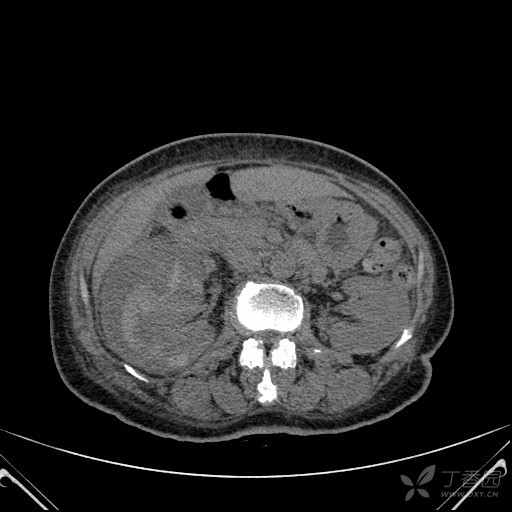

肾包膜下血肿

【病例】肾挫裂伤伴包膜下血肿1例ct影像表现

肾包膜下血肿(i级肾损伤)